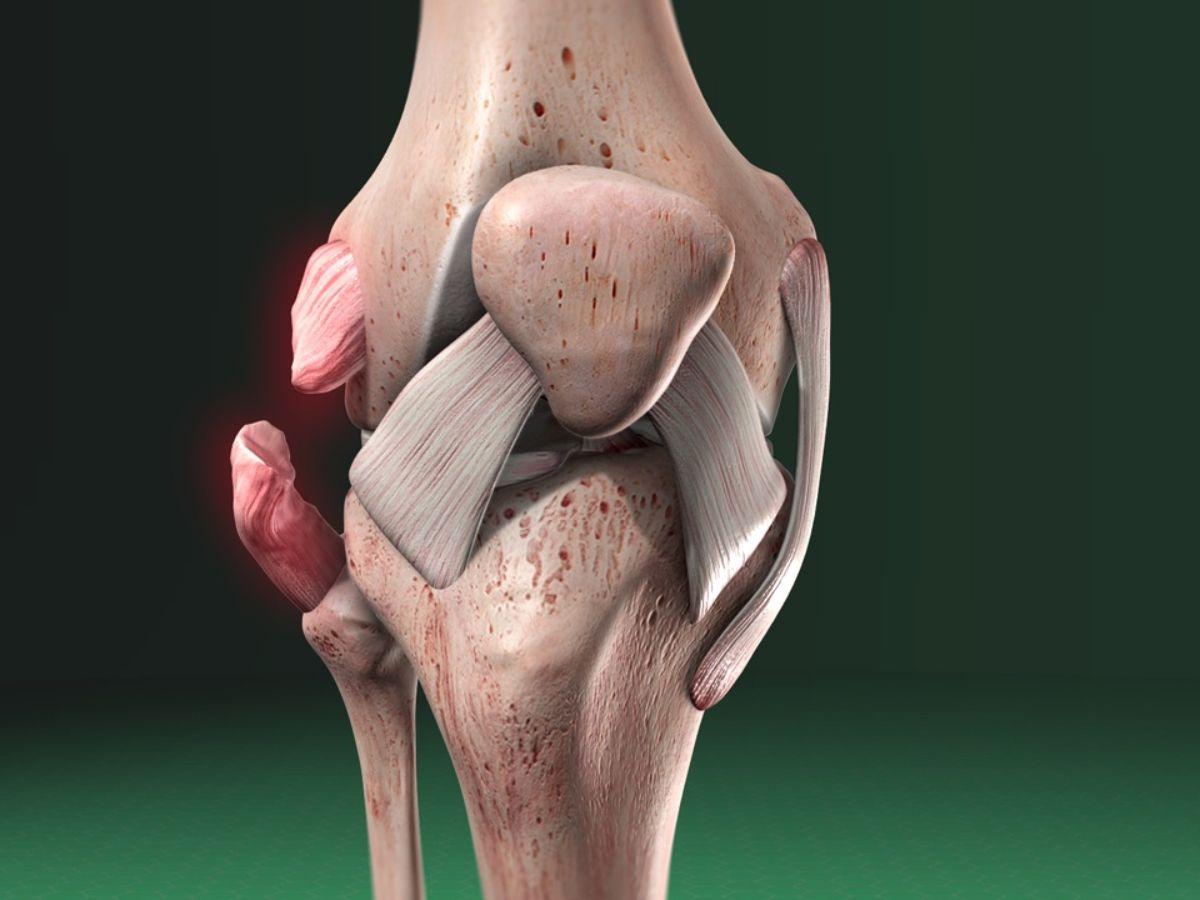

Chấn thương dây chằng

Chấn thương dây chằng khớp gối là khi các hệ sợi dây chằng khớp bị kéo quá căng hoặc rách, đứt trong quá trình vận động hoặc tai nạn nghiêm trọng. Chấn thương này bao gồm bốn loại chính:

Chấn thương dây chằng chéo trước ACL: Chức năng của dây chằng chéo trước là chống sự di chuyển về phía trước của xương mâm chày và giữ cẳng chân không bị xoay vào trong khi di chuyển. Triệu chứng chính khi bị bị chấn thương đầu gối là cảm giác đau dữ dội ngay sau khi hoạt động mạnh, có cảm giác nghe tiếng “rụp” ở đầu gối, phần khớp gối bị sưng vù và khó di chuyển.

Chấn thương dây chằng chéo sau PCL: Dây chằng chéo sau có tác dụng ngăn sự di lệch về phía sau của mâm chày và xương đùi. Khi bị tổn thương, triệu chứng đầu tiên là cảm giác đau nhẹ hoặc vừa phải, chân sưng nhẹ, có cảm giác không ổn định khi di chuyển.

Chấn thương dây chằng trong MCL: Dây chằng trong nằm ở mặt trong khớp gối, có tác dụng duy trì sự ổn định của khớp khi bị ngoại lực tác động. Khi bị tổn thương, phần mặt trong đầu gối sẽ bị đau và sưng, có cảm giác đau đớn khi di chuyển hoặc gập đầu gối.

Chấn thương dây chằng ngoài LCL: Dây chằng ngoài bao bọc ở bên ngoài khớp gối, giúp ngăn cản sự di chuyển của các khớp xương ngoài phạm vi cố định. Khi bị tổn thương sẽ có cảm giác đau và sưng ở mặt ngoài khớp, mất khả năng xoay chân hoặc gập đầu gối.